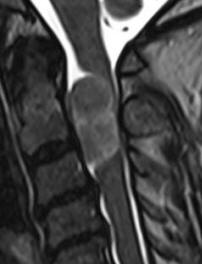

The patient a female 53 years came to the clinic 03-September-2016 complaining of neck and right upper limb pain for 4 years with progressing numbness right hand. MRI cervical spine spine performed 01-September-2016 without report and very bad quality, showing as be an intramedullary mass behind C1-2-3.

On examination, the patient had no pain when turning the head to all direction. There was weak right deltoid 3/5, left 4/5, right biceps -4/5, left 4/5, flexion right hand 3/5, left 4/5, extension right hand -3/5, left 3/5, right triceps 4/5, left 5/5. There was weak dorsiflexion right foot -4/5, left 4/5. The deep reflexes were exaggerated in the right side, but no pathologic reflexes. There was no apparent sensory deficit.

The patient was sent for thorough investigations and MRI cervical spine performed 04-September-2016 showed huge meningioma 33x12.7 mm intradurally pushing the spinal cord to the left. Spectroscopy was typical for meningioma and the mass was lacking fibers. There was and extension to the right C1-2 foramen reaching the vertebral artery pushing it anterior.

In prone position with the use of IOM ISIS, laminectomy of C2-3 and partial of C1 was achieved. The dura was opened slightly right parallel to the midline. The dumbbell-shaped appearance of the tumor was due to right C2 anterior and posterior rootlets, which were constricting the tumor and they were preserved to the end of surgery. The matrix of the meningioma was the right lateral wall of the dura, which was coagulated and piece-meal resection of the tumor was performed. MEP was troubleshooting and not informative. After the resection of the tumor a tiny piece and the emergence of the right C1 was removed trying during that to preserve the rootlets. Using MultiGen, bipolar motor stimulation of right C2 was achieved with 1.0 V. Motor stimulation of the right side of the spinal cord and a brisk response of the right upper and lower limbs was achieved above the tumor resection area. Irrigation of the area with 1 ampoule Papaverine diluted with 20 ml saline. The dura was closed water-tightly. Routine closure of the wound. The patient was sent to MRI before extubation.

Smooth postoperative recovery. She showed deep paralysis of the right upper and lower limbs, which started to improve over several hours. She was sent to the ICU. Figures (14-21) demonstrating the case.

Fig-14: The meningioma in different sections and sequences.